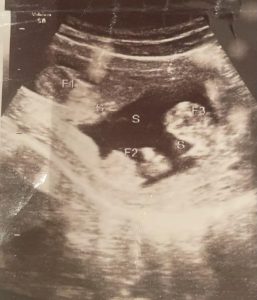

Nigerian singer, Kizz Daniel who celebrated the birth of his twin sons, Jelani and Jalil some months ago has revealed that his girlfriend actually gave birth to triplets. Habaklef Report that The Yeba singer (aka Vado D’Great, Okunrin Meta) made this shocking revelation whilst celebrating the houses he brought for his twins.

According to Kizz Daniels, his girlfriend gave birth to Jamal, Jalil and Jelani. But shortly after his birth, the infant passed away. He noted that the death of the boy hit them hard, but he made a promise to Jamal and Jalil to be the best father to his brothers.

“GOD blessed me with 3 boys a while back; JAMAL, JALIL and JELANI (triplets). 4 days after i lost JAMAL. Nevertheless, I made a promise to him that I’ll be the best father in the whole galaxy to his brothers….. Congrats to the latest Home owners in town , Jelani and Jalil ?? My first gift to my sons“